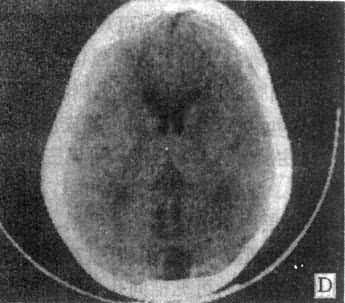

10mm底颅层面 此层面通过眦耳线上方10mm,由前向后可见眼眶上部、蝶窦和中颅凹底、枕骨及枕大孔等颅底结核。20mm蝶鞍层面 可见垂体、四脑室、桥池和桥小脑角池、岩锥与内耳道、前、中和后颅凹脑组织结构。本层面重点观察垂体和后颅凹结构。(图5-1-4A)。30mm鞍上池层面 可见鞍上池呈六角星或五角星形低密度脑脊液间隙,增强CT扫描尚可见脑底动脉环在池内的分布情形(图5-1-4B)。鞍上池后方、环池和四叠体池包绕部分即为中脑。40mm三脑室前部层面 重点观察内囊、基底节和丘脑区(图5-1-4C)。50mm三脑室后部层面除显示内囊、基底节和丘脑区外,同时是观察三脑室后部松果体区重点扫描层面(图5-1-4D)。60mm侧脑室体层面可观察侧脑室体部、三角区和后角(图5-1-4E);增强CT尚可见直窦、上矢状窦和大脑镰强化显影。70mm侧脑室顶层面 可见侧脑室顶部、大脑纵裂、脑皮质和脑髓质(图5-1-4F)。80~100mm脑室上层面 脑皮、髓质、脑沟和大脑纵裂清楚显示。

图5-1-4 正常头部CT扫描

E、侧脑室体部层面 F、侧脑室顶层面